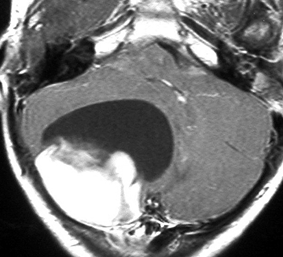

7歳児の小脳半球にある標準リスクの髄芽腫です。画像を一見すればこの髄芽腫は治るであろうと予測します。

手術で完全摘出し,退形成性髄芽腫の病理診断で,脳脊髄照射と局所照射54グレイ,シスプラチンベースの化学療法を6コース加えましたが,半年後に激しい播種再発を生じました。